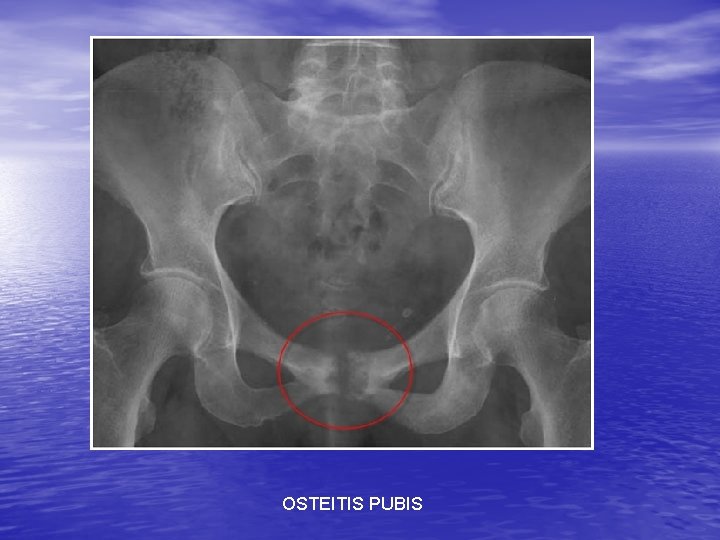

PELVIC CONDITIONS • Hip Pointer: contusion to the iliac crest • Osteitis Pubis: Pull of muscles from the pubis. Common in runners • Athletic Pubalgia: Chronic pubic region pain. • Stress Fx • Avulsion Fx and apophysitis: Inflam of the apophyses of the hip

OSTEITIS PUBIS